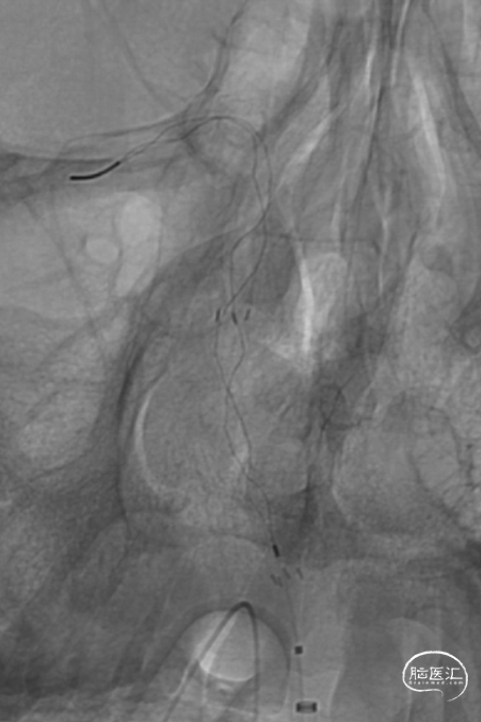

加奇Tethys®中间导引导管到位,明确既往支架位置。但中间导管通过困难。

微导丝微导管通过闭塞段,在右侧大脑后动脉手推造影证实真腔,明确闭塞段,可见造影剂返流至基底动脉尖部,且证明闭塞确为支架内再狭窄导致闭塞。

释放加奇4.0mm*30mm Syphonet®取栓支架,可见支架通体显影。